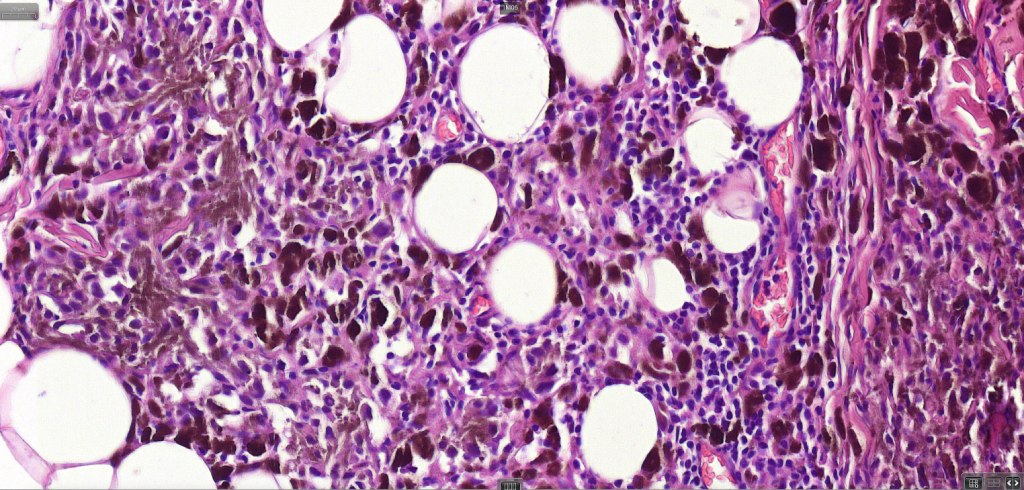

3. a deep penetrating nevus like lesion showing obvious signs of malignancy including greater pleomorphism than is usually seen combined with excessive mitotic activity, deep mitoses and atypical forms

4. melanoma which shows a deep penetrating architecture although the cytology remains epithelioid throughout